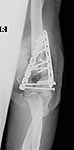

He was treated with IV antibiotics and no sign of infection was seen. After antibiotics were stopped, he still showed no sign of infection. He was offered a total elbow replacement which he refused since he has a handicapped child that he needs to care for, and he did not want to accept the lifting restrictions. He was offered an elbow fusion which he refused because he did not want the stiffness, but he did agree to fixation across the elbow without taking out the joint, even knowing that he would still have stiffness and even with later soft tissue release might not be any different than a fusion. The second revision including cross elbow fixation is in files (2nd revision).

2nd revision

This surgery was done 9/27/04. He was grafted with DBX and BMP, and debrided to bleeding bone with good contact, and compressed with a lag screw. At surgery there was no sign of infection. 3 sets of deep bone cultures came back "no growth" and a bone biopsy did not reveal any inflammatory cells. Sed rate was 21 and C-reactive protein 0.4.

He continues without sign of infection. But his sed rate is 65 and C-reactive protein 21. Despite cast immobilization, his current x-rays (11/17/04) show another failure of fixation (files current)... He still does not want replacement.

current